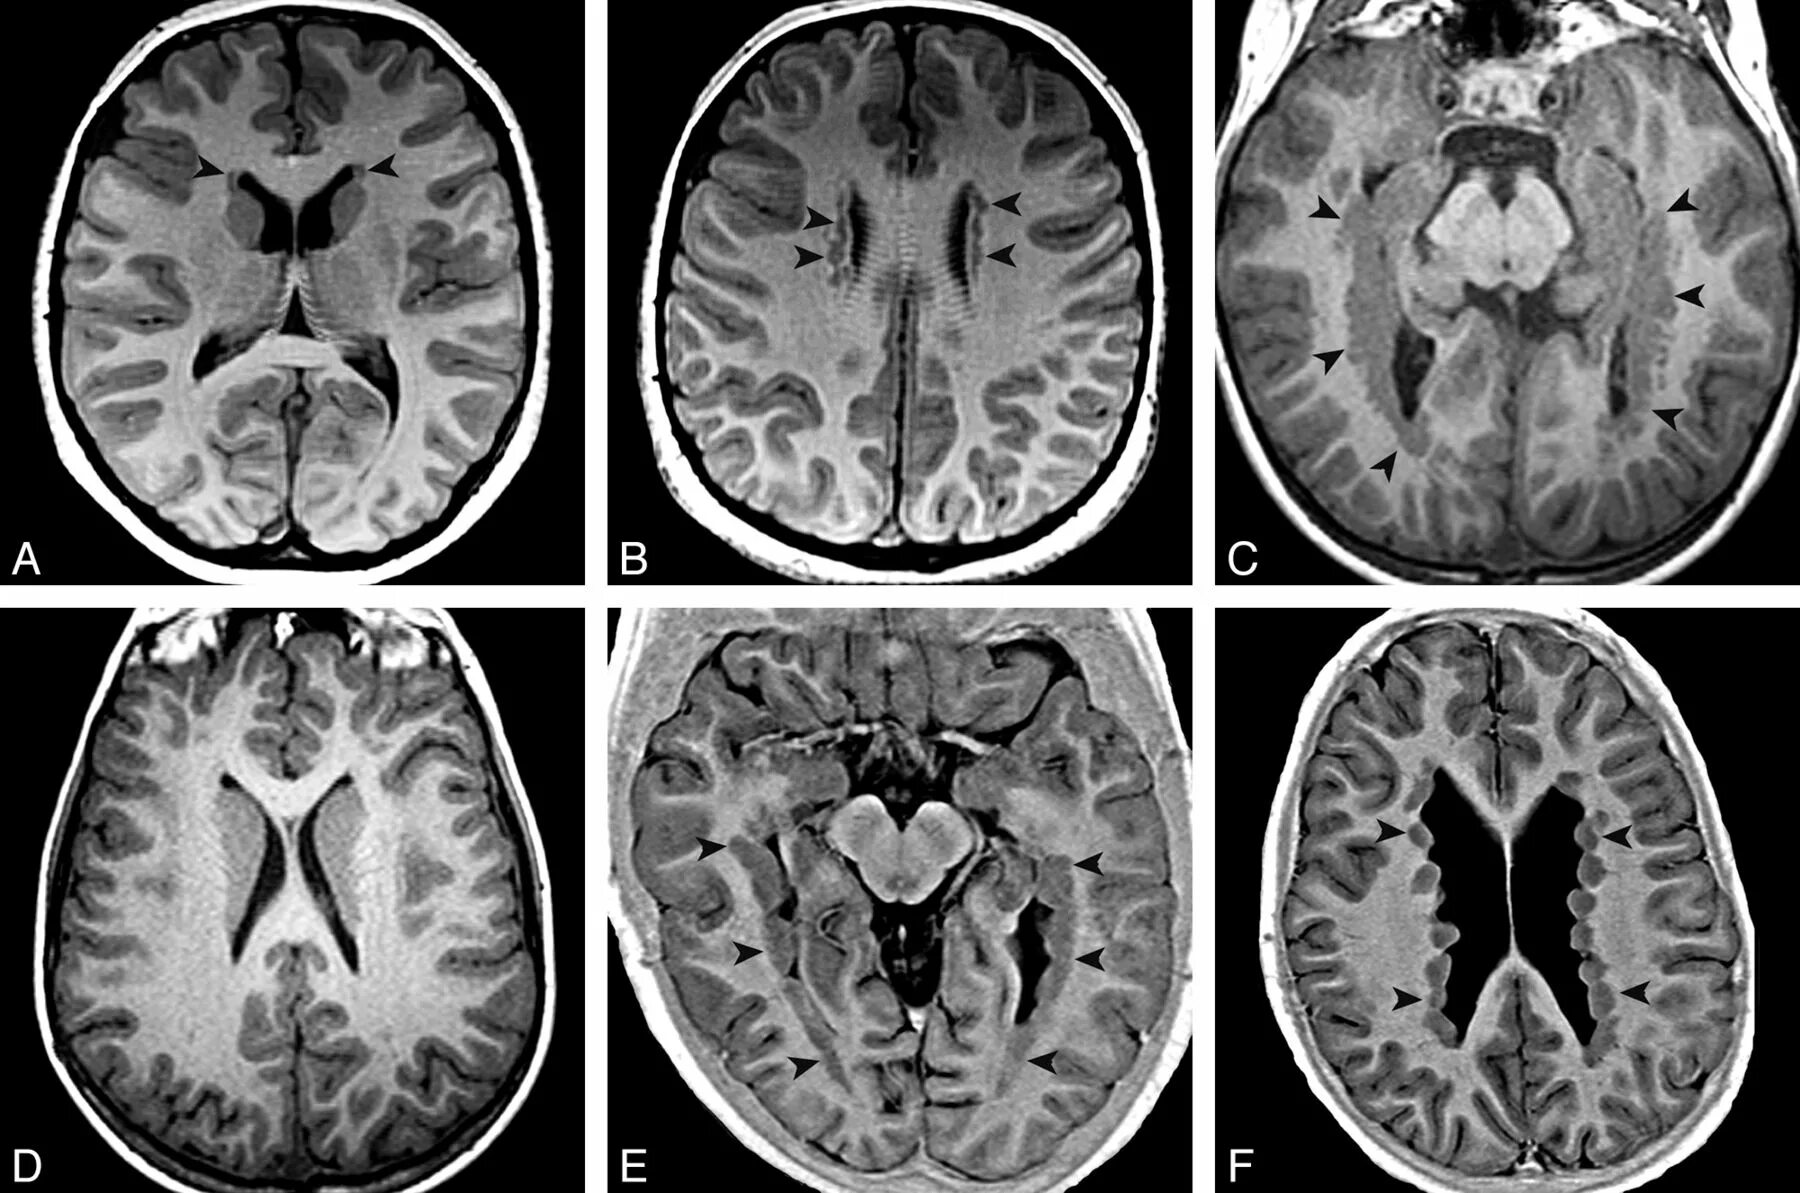

Субкортикальные очаги в лобных долях